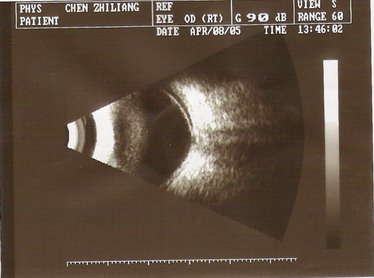

2005年4月8日B超:右眼玻璃体轻度混浊,右眼视网膜脱离,视盘凹陷(青光眼型)

200548因视物不清来诊,查体:VOD0.25VOS1.0,右眼瞳孔直径5.0mm(对侧3.0mm),光反应迟钝,周边前房3/4CT,眼底视乳头色正,血管偏位,C/D=0.6,眼底鼻侧视网膜略显平脱。眼压:右25.3mmHg,左17.0mmHgB超提示右眼视网膜脱离,视盘凹陷(青光眼型)。